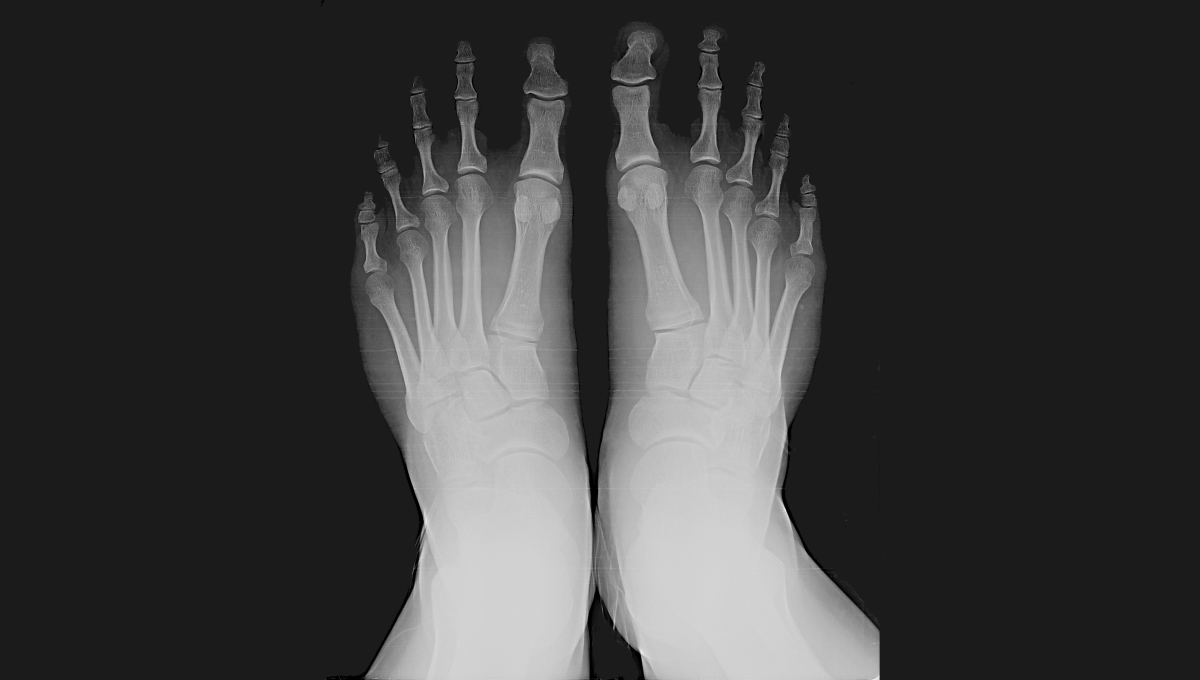

Shoe Fitting Xray . How do those shoes fit? The shoe fitting fluoroscope was a common fixture in shoe stores during the 1930s, 1940s and 1950s. Too wide in the heel? How do you tell if a shoe is a good fit? Too tight in the toes? A typical unit, like the adrian machine shown here, consisted of a vertical wooden cabinet with an opening near the bottom into which the feet were placed.

The shoe fitting fluoroscope was a common fixture in shoe stores during the 1930s, 1940s and 1950s. Too wide in the heel? A typical unit, like the adrian machine shown here, consisted of a vertical wooden cabinet with an opening near the bottom into which the feet were placed. How do you tell if a shoe is a good fit? How do those shoes fit? Too tight in the toes?

Foot and shoe Xray, 1896 Stock Image C034/5128 Science Photo Library Shoe Fitting Xray The shoe fitting fluoroscope was a common fixture in shoe stores during the 1930s, 1940s and 1950s. Too wide in the heel? A typical unit, like the adrian machine shown here, consisted of a vertical wooden cabinet with an opening near the bottom into which the feet were placed. Too tight in the toes? How do you tell if a. Shoe Fitting Xray.